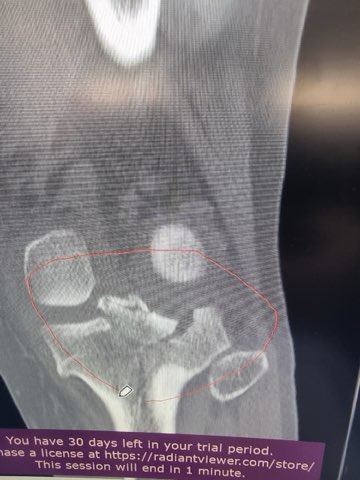

MRI, X-Ray 가지고 있는 사진 첨부했습니다.

무릎 골절, 견갑골 골절, 무릎인대 파열, 대퇴골의 골절, 경골 골절, 흉추 골절, 다발의 타박상, 다발의 찰과상, 뇌진탕